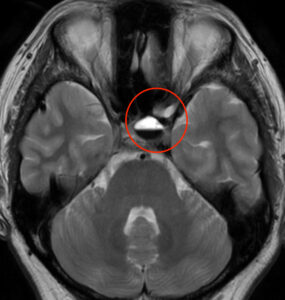

MRI検査をしたところ、

目の奥にある下垂体という部分に異常信号を認めました。